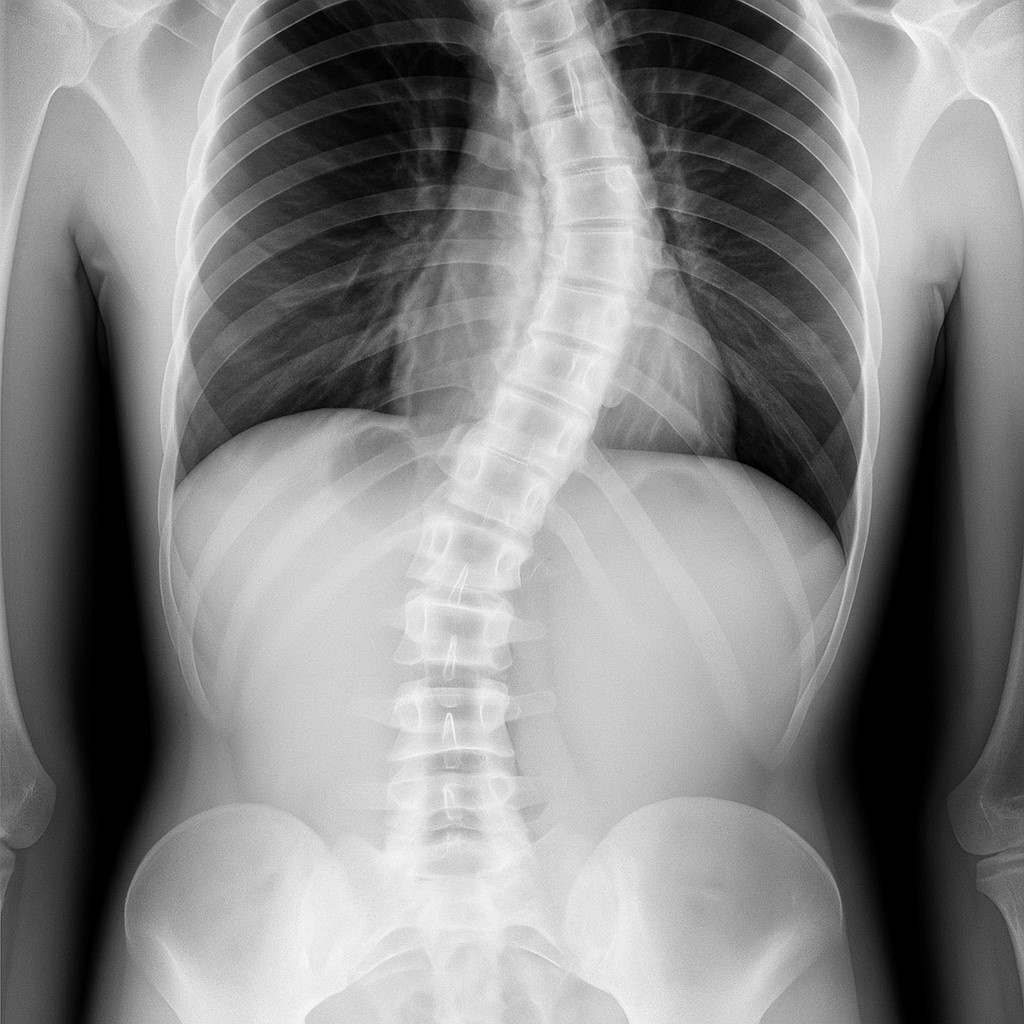

Судьба-насмешница обошлась с ней очень жестоко. Когда Леокадия была ещё совсем маленькой, но абсолютно нормальной девочкой, ей «посчастливилось» очень неудачно упасть с каменных ступенек и сильно повредить себе позвоночник и грудную кость. Врачи поначалу даже не были уверены, сможет ли она вообще когда-то ходить. Но спустя какое-то время, этой сильной, жизнерадостной девочке всё-таки удалось, благодаря её решительности и упорству, подняться с больничной койки и медленно, но уверенно начать заново делать свои «первые шаги»...

Вроде бы всё кончилось хорошо. Но через какое-то время, к всеобщему ужасу, у неё спереди и сзади начал расти огромный, совершенно жуткий горб, который позже буквально изуродовал её тело до полной неузнаваемости…»